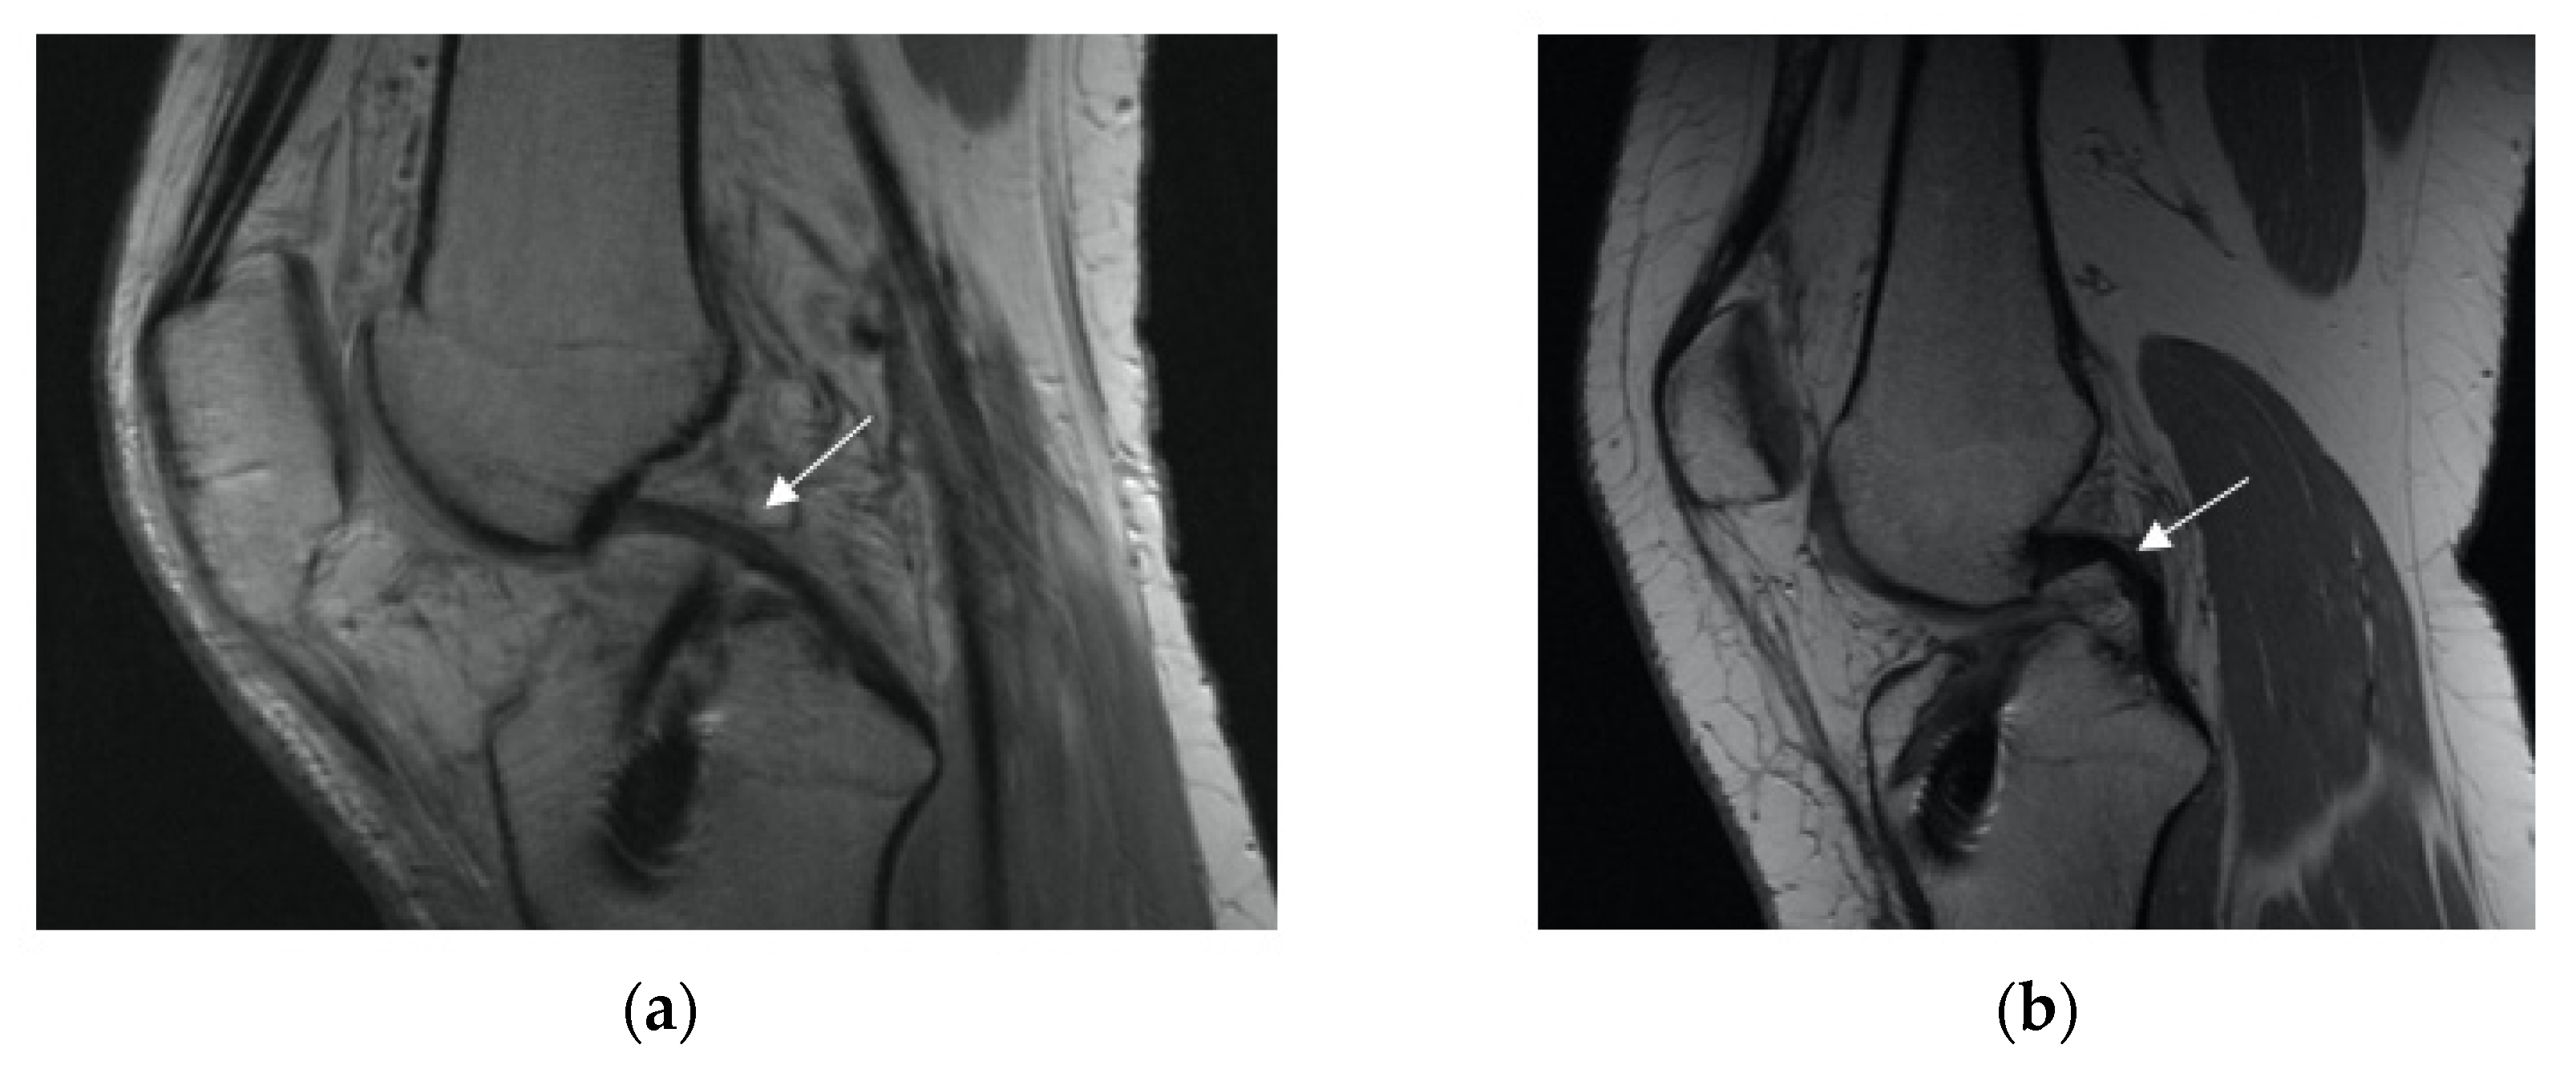

3.2.2. Posterior Cruciate Ligament (PCL) Buckling (Subluxation)

3.2.3. Anterior Tibia Subluxation

4. Discussion